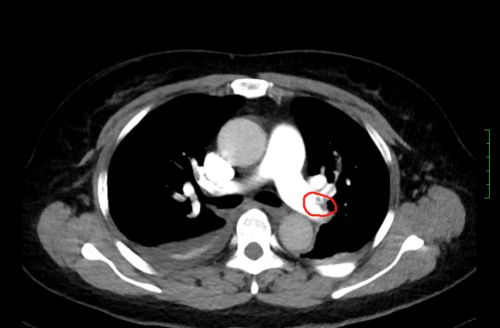

ct上可以看到,患者双侧肺动脉均有血栓形成。

值班医生立即向上级医生汇报,考虑肺栓塞可能,立即进行抗凝治疗,同时迅速陪同病人前往放射科做肺部CTA检查。放射科开通绿色通道,迅速完成检查,CT结果提示:肺动脉栓塞高度可疑。主管医生立即向科主任尹新民教授汇报。尹新民主任一边赶赴医院,一边指示值班医生请呼吸内科、心内科、介入血管外科、重症医学科、超声科等科室紧急会诊。在排除过敏性、心源性、感染性呼吸困难后,结合患者的症状,会诊专家一致考虑为“急性肺栓塞”。这是一种死亡率极高的临床急危重症,常发生于重大创伤、大型外科手术等患者,具有起病急、变化快、症状不典型的特点,极易误诊或漏诊。如抢救不及时,死亡率几乎为百分之百。

情况十万火急,尹新民主任边现场组织抢救,边将情况汇报给向华副院长,向华副院长立即调度全院各相关科室予以协助。一场与生命的赛跑由此拉开!超声科紧急为患者进行床旁彩超,找到肺动脉栓塞的“罪魁祸首”为左下肢静脉血栓。在呼吸治疗组的协助下,医护人员携带转运呼吸机快速运送方女士至介入手术室。介入血管外科紧急安排了手术医生和手术间,由张永琎副主任医师等为患者施行“肺部血管造影”,明确诊断为双肺动脉急性栓塞,随即为其实施“双肺动脉尿激酶冲击溶栓、下腔静脉滤器植入术”。术后,患者肺动脉供血明显改善,血氧饱和度立即回升,被送往重症医学一科继续治疗。